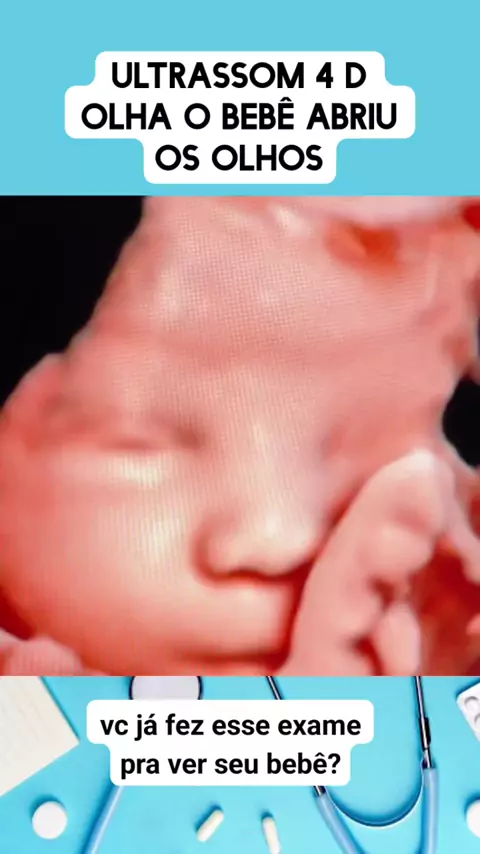

ultrassom 4d #medico #medicina #Saúde #viraliza